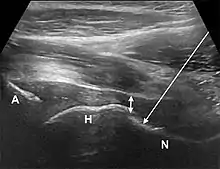

- The anterior longitudinal approach: the probe is aligned along the long axis of the femoral neck. The needle is introduced from an anteroinferior approach and is passed into the anterior joint recess at the femoral head-neck junction.

- The anterolateral approach, with the ultrasound probe oriented axially and the femoral head and acetabular rim in view. This often shortens the distance from needle skin entry to joint compared to the longitudinal approach making it a useful approach in larger patients. The introduced needle remains lateral to the femoral neurovascular bundle, and the needle is advanced until its tip rests on the femoral head.